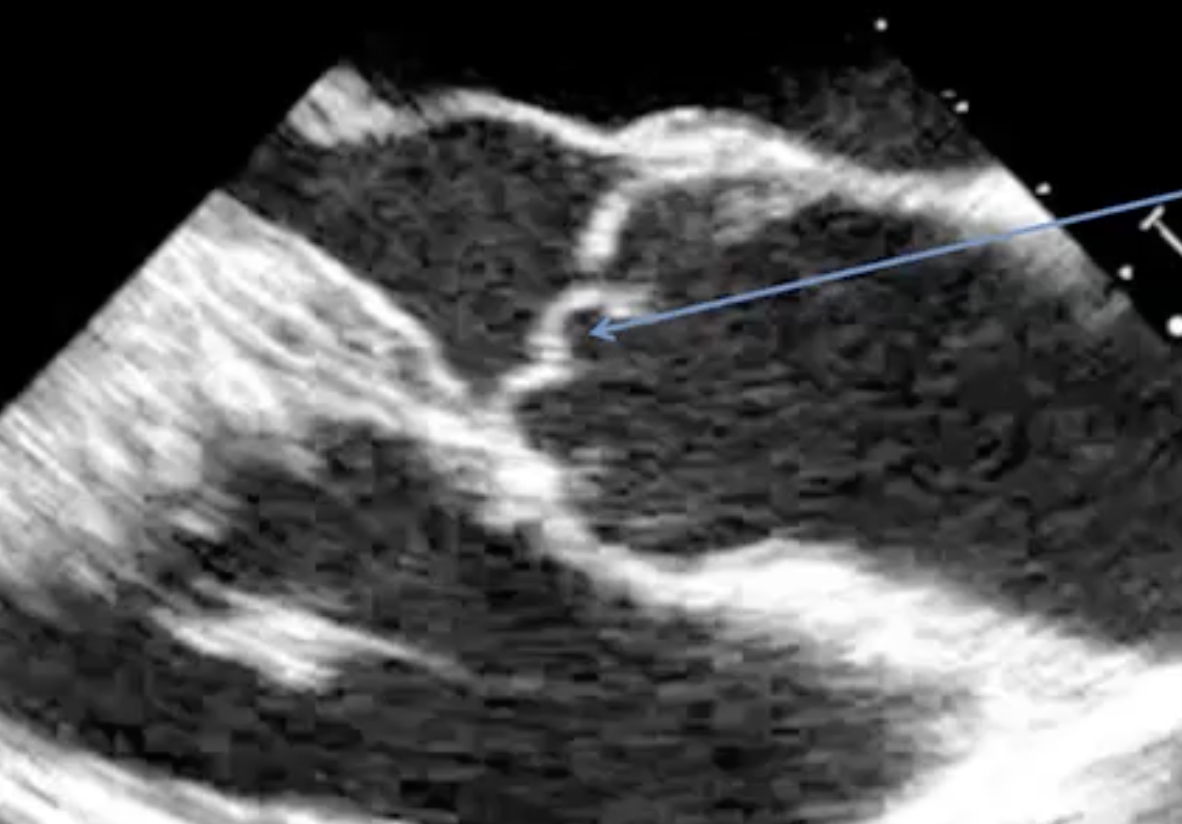

What are the best views and velocity scale settings for diagnosis of AR?

What are the steps/parameters to evaluate AR severity?

In addition to severity of AR what other parameters should be assessed/obtained in the evaluation?